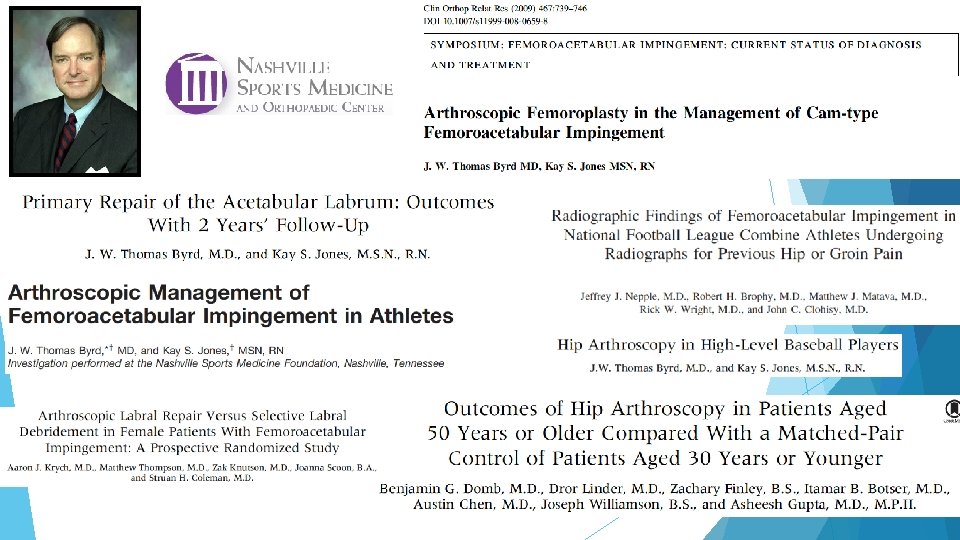

Where is the evidence?